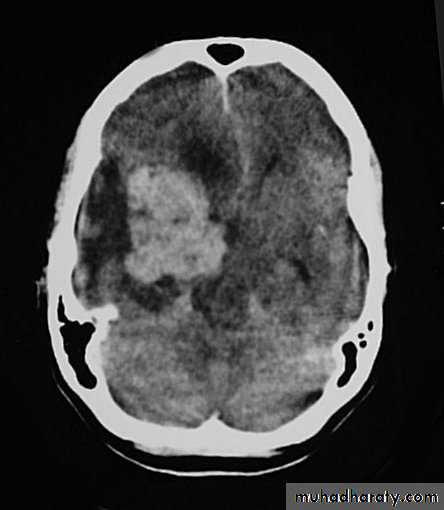

Metastatic Brain Tumours Pre contrast CT

Metastatic Brain Tumours Post contrast CT